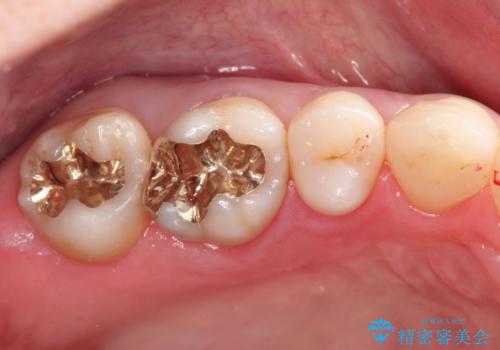

むし歯の治療。ゴールドインレーによる修復

- 定期健診にてむし歯を認めたためゴールドインレーにて治療を行いました。

ゴールドインレーは適合が良く、割れることもないため、長期的に安定した治療法となります。